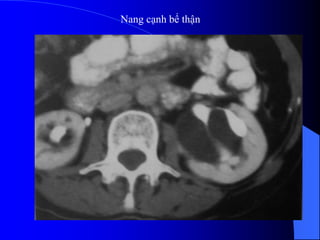

3.3. Nang caûnhbãø tháûn Täøn thæång laình tênh Xaøy ra åí moüi læïa tuäøi Thæåìng khäng coï triãûu chæïng, træì khi nang låïn cheìn vaìo bãø tháûn gáy âau læng, cheìn vaìo âäüng maûch tháûn gáy tàng huyãút aïp. Nang hçnh thaình do âæåìng baûch maûch giaîn. Nang chæïa dëch coï albumine, lipide vaì cholesterole. Nang thæåìng nhiãöu äø khäng thäng våïi ÂBT, âáøy bãø tháûn vãö mäüt phêa hoàûc bao quanh caïc ÂBT vaì keïo daìi caïc âaìi tháûn.

• 62.

Trãn NÂTM coïthãø tháúy ÂBT bë âeì âáøy. Trãn siãu ám laì khäúi räùng ám, tàng ám sau, thaình moíng, åí xoang tháûn. Phán biãût våïi æï næåïc âaìi bãø tháûn, åí âáy caïc nang caûnh bãø tháûn khäng thäng nhau.

• 63.

• 64.